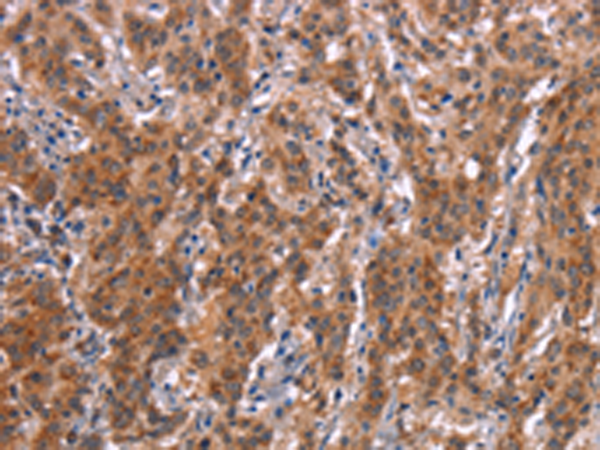

分类: 科研抗体货号: P04874别名: F1AA; F1A-ALPHA; FEM1-beta应用: WB,IHC反应种属: Human, Mouse, Rat